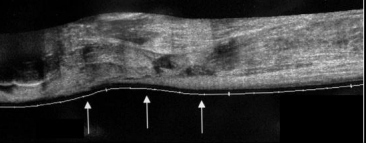

Een scheur van de achillespees

Echografie

Acute fasciitis plantaris

Bekijken we via een echografie. De hyperemie die aanwezig is , wijzen op acute inflammatie.